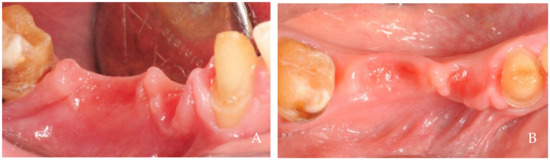

2. Clinical Examples of Oral Soft Tissue Growth